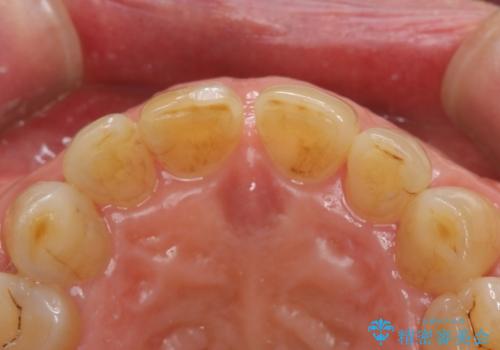

- 前歯のすきっ歯を気にして来院された患者様です。

矯正かオールセラミックか、治療の選択がありましたが、ご年齢や色の濃い点を考慮してオールセラミッククラウンにて補綴することとしました。